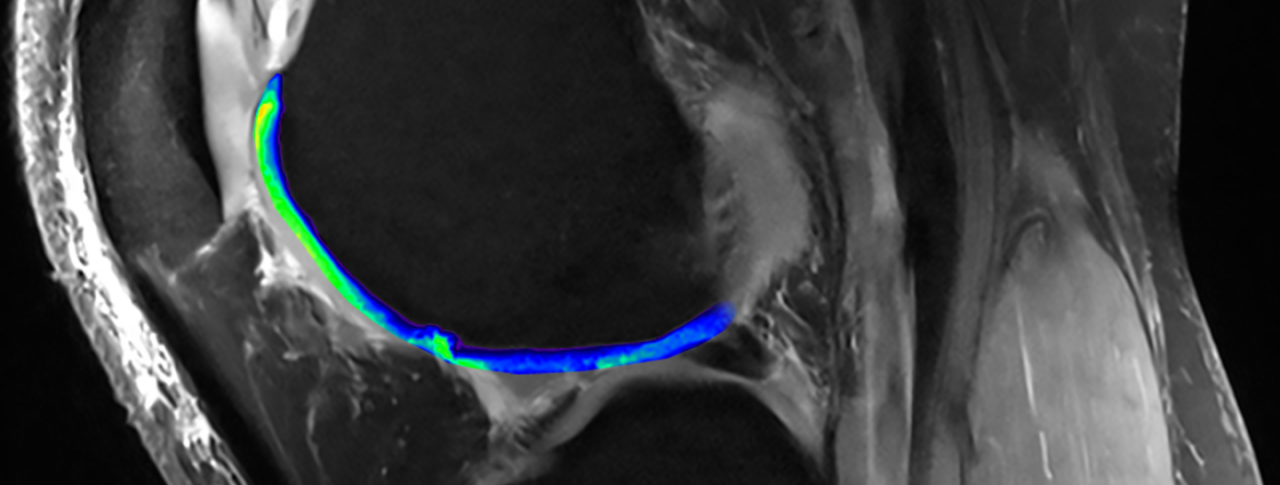

MRI tech reveals cartilage quality

Traditional MRI uses magnetic pulses to induce a signal from water molecules in the body. This technology differentiates cartilage (blue/light green) from bone. Advanced MRI uses the same approach but applies it to sodium. The tech identifies proteoglycans (bright green), the special ingredient in high-quality cartilage. Regions devoid of this sodium signal point to defective cartilage. Images courtesy Siegfried Trattnig (modified by Fidelis Onwubueke)

In addition to using a powerful MRI machine, Trattnig has developed techniques that expand the range of materials MRIs can detect. For instance, the technology can detect levels of proteoglycan, the special ingredient in high-quality cartilage.

These MRI images also show gaps in the cartilage (in darker blue above), which indicate damage. NIBR researchers are investigating a way to fill those gaps with high-quality cartilage using an experimental regenerative medicine. By using advanced MRI in their clinical trials, they could have a way to measure the quality of the cartilage regenerated without having to put patients through painful biopsies.